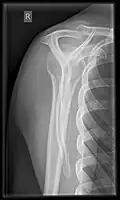

- Transaxillary projection

The arm should be abducted 80 to 100 degrees. This method reveals:[26]

- The horizontal alignment of the humerus head in respect to the socket and the lateral clavicle in respect to the acromion

- Lesions of the anterior and posterior socket border, or of the tuberculum minus

- The eventual non-closure of the acromial apophysis

- The coraco-humeral interval

Transaxillary conventional radiography -